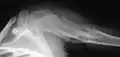

X-ray showing enchondromas localized in the humerus of a 37-year-old patient affected with Ollier disease